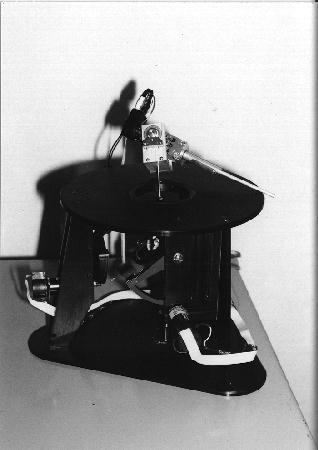

The robots used for automated surgery tend, at the present time, to be adapted industrial robots; for example, the PUMA robot arm. The reasons behind this are predominantly financial ones. Investing in the research and development of a robot for a specific task is highly expensive - costs running into millions of pounds, with no guarantee that a suitable product will be the outcome. Another hurdle is the lack of official safety guidelines and standards. Having brought up the fact that the surgeon is reliant upon the engineering behind the tools that they are using, it is clear that companies would not wish to risk possible legal proceedings should one of their products fail. (These issues will be further discussed in the section on safety). As it stands, industrial robots are adequate for the tasks involved, although it is hoped (and expected) that, in the future, surgery- specific robots will be developed and will become an industry of their own. Once the robotic procedure is initiated, sensors collect real-time data from the operating site and pass this to a display, via which the surgeon observes the operation. The type of sensor that seems to best suit the surgical application is the use of infra-red transmitters on the robot's 'joints', that are detected by cameras in the operating theatre (currently under commercial development by General Electric). From these, the exact position of the robot's appendages can be gauged and relayed back to the surgeon's display. It is an issue as to what control a surgeon should have when overseeing an automated surgery - as they may do more damage than good if they intervene. The most common arrangement is to have a 'stop' switch and perhaps a 'redo' control. Sensing the patient, intra-surgically, is fairly simple when using fiducials (the fiducials are specially made from materials that are easily detectable under the system being used). This is not the case, however, when using the preferred surface techniques. Here a variety of systems are under consideration, including an ultrasound sensor or an x-ray sensor - both mounted on a 'C-arm' so that they can move around the whole area of the patient. |